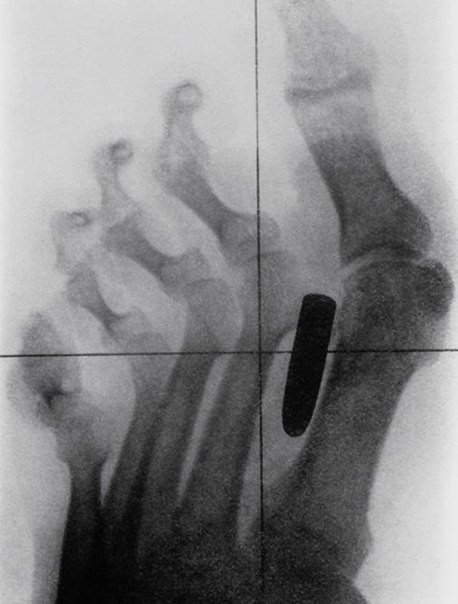

8> Una antigua radiografía de un soldado de la época de la Guerra Anglo-Bóer (1899-1902); una bala se quedó atrapada entre el pulgar y el índice. ### Response: